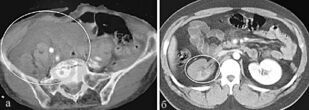

Во второй части учебного пособия «Сочетанная закрытая травма живота и органов забрюшинного пространства» отражены принципы хирургического лечения закрытых травм живота. Подробно изложены классификация, клиническая картина, современные методы диагностики и лечения повреждений паренхиматозных и полых органов живота и забрюшинного пространства. Отдельные главы посвящены технике ревизии брюшной полости, реинфузии крови, методам завершения хирургической операции, профилактике послеоперационных осложнений. Прилагаемые задания для самопроверки затрагивают все основные аспекты рассматриваемых патологий.